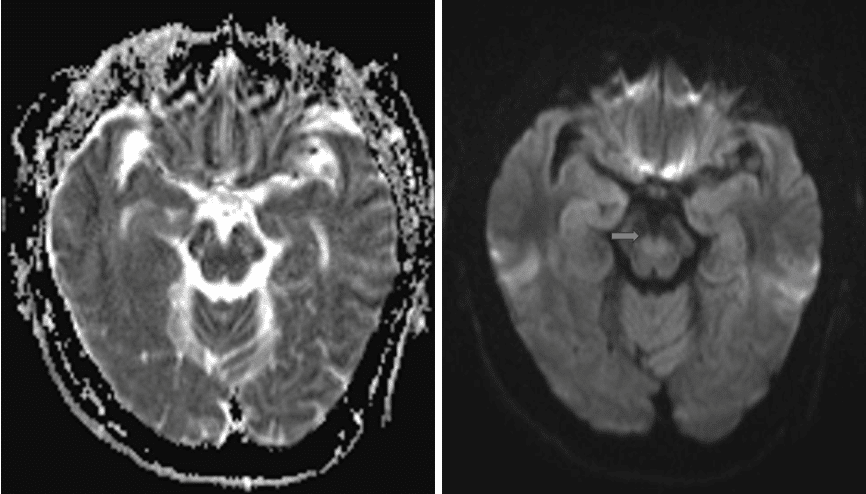

头MR(2017-05-09 依次为ADC、DWI序列)见中脑弥散信号偏高;同日,电解质化验提示 Na 126mmom/L